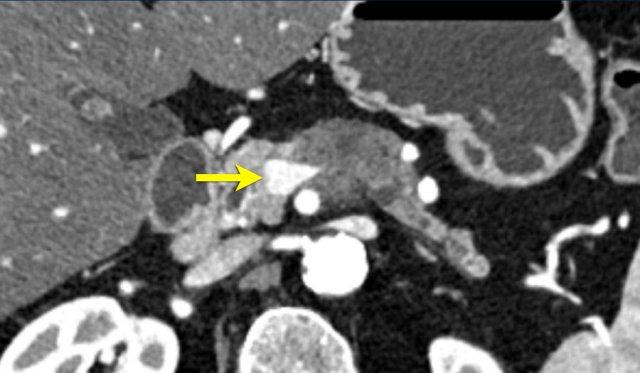

Việc sử dụng tái tạo đa mặt phẳng (multiplanar reformation) giúp cải thiện hiệu quả chẩn đoán tổng thể của CT, như được minh họa trong trường hợp này.

Tái tạo mặt phẳng coronal cho thấy một khối u nhỏ ở đầu tụy (đầu mũi tên) gây tắc nghẽn ống mật chủ.

Có vẻ chỉ có tiếp xúc hạn chế với tĩnh mạch cửa (mũi tên).

Tiếp tục xem các hình ảnh tiếp theo.

Tái tạo đa mặt phẳng vuông góc với tĩnh mạch cửa cho thấy mức độ tiếp xúc với tĩnh mạch cửa rộng hơn, từ 90 đến 180 độ (mũi tên).

Khi không có bất thường bờ viền, trường hợp này được phân loại là có thể cắt bỏ giới hạn (borderline resectable) theo tiêu chí DPCG, nhưng có thể cắt bỏ (resectable) theo tiêu chí NCCN.

Phẫu thuật cắt bỏ không kèm tái tạo tĩnh mạch cho kết quả R1, tức là có xâm lấn vi thể của khối u tại diện cắt.